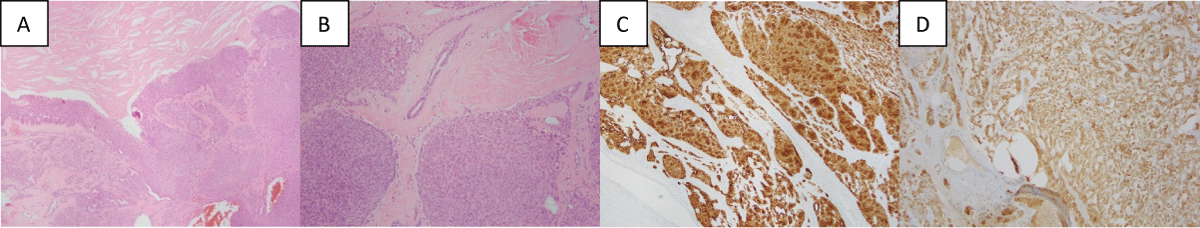

A Gram’s stain for bacterial and fungal cultures returned negative results. Sectioning revealed a collapsed, smooth-walled unilocular cyst, containing golden-brown, soft, friable debris. Histologically, the lesion had mixed cystic, solid, and mucinous/clear cell areas. The lesion was well indicated and lacked significant cytologic atypia, mitotic activity, and necrosis. The S100 and pankeratin exhibit positive staining which suggests that this lesion is not melanoma (Figure 4).

Figure 4: Histological and immunological images from excised hidradenoma: (A) Photomicrograph of hematoxylin-eosin (x4) showing an area of a proliferation of epithelial cells arranged in both solid nests and mucinous/clear cell areas which are a classic feature of hidradenoma; (B) Photomicrograph of hematoxylin-eosin (x10) further depicting the solid cellular nodules containing the thick, eosinophilic fibrous septa and hyalinized stroma; (C) Photomicrograph of S100 demonstrating areas of diffuse cytoplasmic brown positivity within the cells which is suggesting a significant portion of adnexal epithelial cells. Photomicrograph of Pankeratin displaying widespread brown staining which is a marker for epithelial cells. View Figure 4